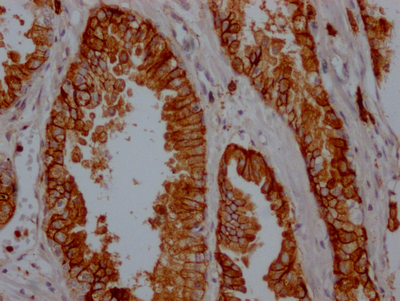

CSB-RA796695A0HU

Tested Applications:

ELISA, WB, IHC

| CD38 | CD38 Recombinant Monoclonal Antibody | Human | ELISA, WB, IHC | CSB-RA796695A0HU |